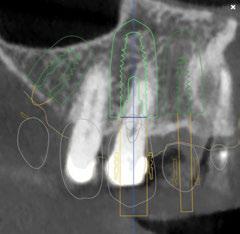

A tenor del estado oral proponemos múltiples opciones terapéuticas, consensuando entre paciente y facultativos una rehabilitación implantoprotésica fija superior e inferior. Debido a la lejanía de la residencia de la paciente, y motivados por las necesidades estéticas que esta exige, consideramos realizar una carga inmediata impresa con resina definitiva el mismo día de la cirugía. Tras el escaneado intraoral con el escáner Dexis IS3700 (Figuras 7 y 8) y realización de CBCT, subimos los ficheros a la plataforma Bego Guide,

procediendo a realizar una solicitud de encargo a través de un formulario. Antes de 72 horas recibimos una propuesta terapéutica. En ella se facilitan vistas 3D detalladas, así como valoraciones y consideraciones a tener en cuenta durante el fresado y la inserción de los implantes (Figuras 9 a 19). Decidimos realizar extracción de todas las piezas remanentes, dada su nula viabilidad a corto-medio plazo y en Bego (a través del portal) proponen mantener 3 piezas (las más viables técnicamente) en cada arcada para proporcionar el anclaje óptimo de la

Figura 9. Propuesta de planificación maxilar con encerado diagnóstico digital. Se visualiza emergencia de los implantes y emergencia protésica con pilares angulados.

Figura 10. Propuesta de planificación maxilar con encerado diagnóstico digital. Destaca la angulación del implante 1.6 esquivando el seno maxilar con un ángulo de inserción de 30 º y una emergencia protésica verticalizada.

Figura 12. Encerado diagnóstico digital teniendo en consideración un aumento de la dimensión vertical.

Figura 13. Representación gráfica de la futura colocación de los implantes y su relación con la rehabilitación.

16. Superposición radiológica implante 45 angulado, teniendo en consideración el encerado diagnóstico y preservando estructuras nerviosas.

Figura 14. Representación tridimensional. Destaca la protección de estructuras nobles (nervio mentoniano) al presentar un implante angulado con íntima relación.

Figura 15. Visión general tridimensional. Destaca la uniformidad en la disposición de los implantes. En amarillo emergencia implantológica y en gris emergencia protésica mediante pilares transepiteliales angulados multiplus.

17. Implante 31

18. Implante 14.

19. Superposición radiológica considerando encerado diagnóstico en el 1 er cuadrante.